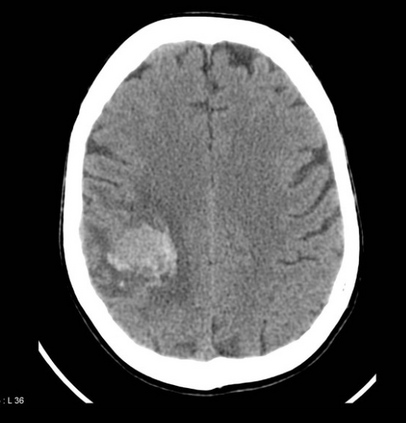

In this study, we aim to initiate the development of Radiology Foundation Model, termed as RadFM.We consider the construction of foundational models from the perspectives of data, model design, and evaluation thoroughly. Our contribution can be concluded as follows: (i), we construct a large-scale Medical Multi-modal Dataset, MedMD, consisting of 16M 2D and 3D medical scans. To the best of our knowledge, this is the first multi-modal dataset containing 3D medical scans. (ii), We propose an architecture that enables visually conditioned generative pre-training, allowing for the integration of text input interleaved with 2D or 3D medical scans to generate response for diverse radiologic tasks. The model was initially pre-trained on MedMD and subsequently domain-specific fine-tuned on RadMD, a radiologic cleaned version of MedMD, containing 3M radiologic visual-language pairs. (iii), we propose a new evaluation benchmark that comprises five tasks, aiming to comprehensively assess the capability of foundation models in handling practical clinical problems. Our experimental results confirm that RadFM significantly outperforms existing multi-modal foundation models. The codes, data, and model checkpoint will all be made publicly available to promote further research and development in the field.